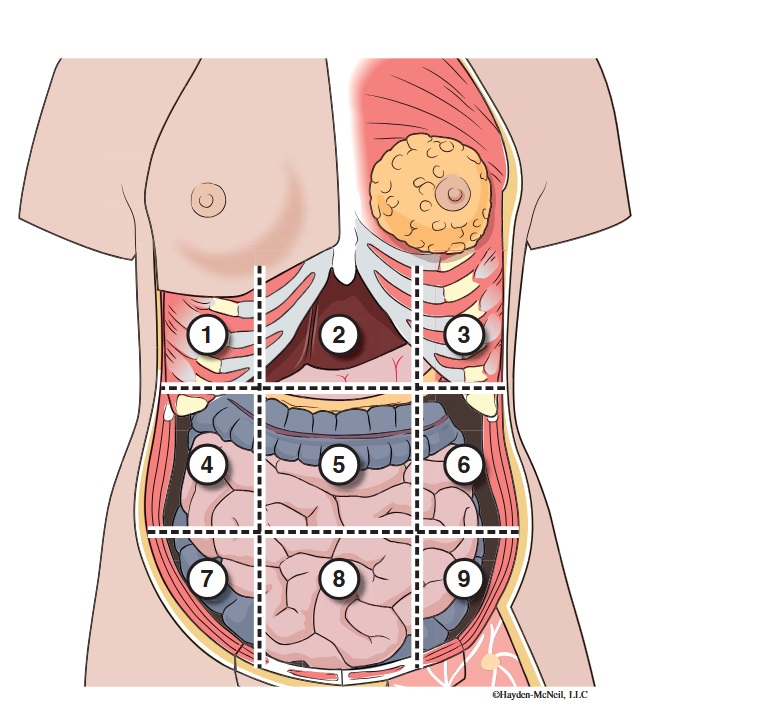

What abdominal region is labeled #1?

right hypochondriac

What abdominal region is labeled #2?

epigastric

What abdominal region is labeled #3?

left hypochondriac

What abdominal region is labeled #4?

right lumbar

What abdominal region is labeled #5?

umbilical

What abdominal region is labeled #6?

left lumbar

What abdominal region is labeled #7?

right iliac/ inguinal

What abdominal region is labeled #8?

hypogastric

What abdominal region is labeled #9?

left illiac/ inguinal

What organs are apart of the right hypochrondriac region?

right lobe of liver, gallbladder, right adrenal gland

What organs are apart of the epigastric region?

pyloric end of stomach, duodenum, pancreas

What organs are apart of the left hypochondriac region?

stomach, spleen, left adrenal gland

What organs are apart of the right lumbar region?

ascending colon, right kidney, portion of small intestine

What organs are apart of the umbilical region?

omentum, mesentery, small intestine

What organs are apart of the left lumbar region?

descending colon, left kidney, portion of the small intestine

What organs are apart of the right iliac/ inguinal region?

cecum of large intestines, appendix, right ovary

What organs are apart of the hypogastric region?

ileum, bladder, uterus

What organs are apart of the left iliac/ inguinal region?

sigmoid colon, left ureter, left ovary